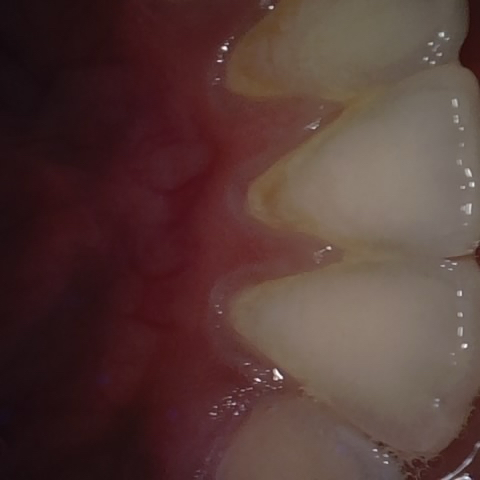

Image 239 / 313

NHD25470

Annotated as "Good"

Original Image Rendering Image